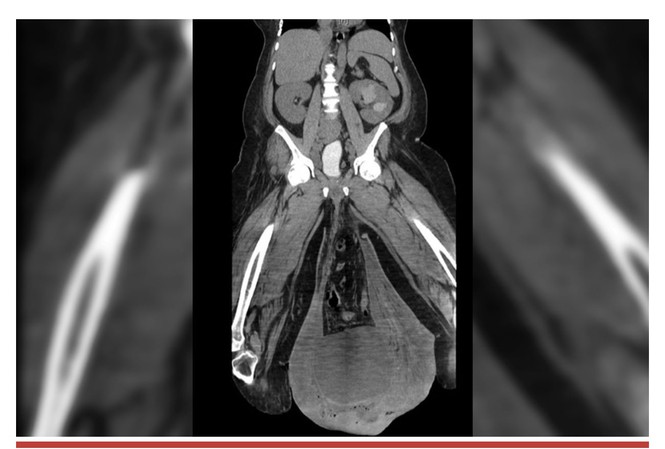

Hình ảnh chụp cắt lớp tinh hoàn của người đàn ông Panams

Khi được chuyển đến bệnh viện, bộ phận sinh dục của anh ta sưng to với chu vi đo được là hơn 30cm - lớn hơn một quả bóng rổ tiêu chuẩn. Việc thăm khám sơ bộ cho thấy, tinh hoàn của anh ta phình ra to đến nỗi chạm sàn nhà, khiến anh ta không thể di chuyển mà không có sự trợ giúp của người khác.

Tình trạng bệnh nhân rất phức tạp do phù bạch huyết độ 4 (sưng) ở háng và chân phải, một biểu hiện thường có ở những người mắc bệnh chân voi - một bệnh do muỗi gây ra khiến chân và bộ phận sinh dục bị ảnh hưởng.

Kết quả chụp CT cho thấy thoát vị ở háng, một túi khí 12,8 cm dưới da và một bể chứa nước tiểu đã khiến thận của anh ta phồng lên.